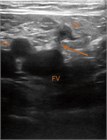

表在静脈の血栓症は,深部静脈血栓症と同じ危険因子や静脈瘤によって起こりうる.表在静脈血栓症が塞栓を起こすことはまれであるが,時間の経過とともに深部静脈系に及ぶことがあり,その際には塞栓のリスクははるかに高くなる.本章では,診断と管理について説明する.